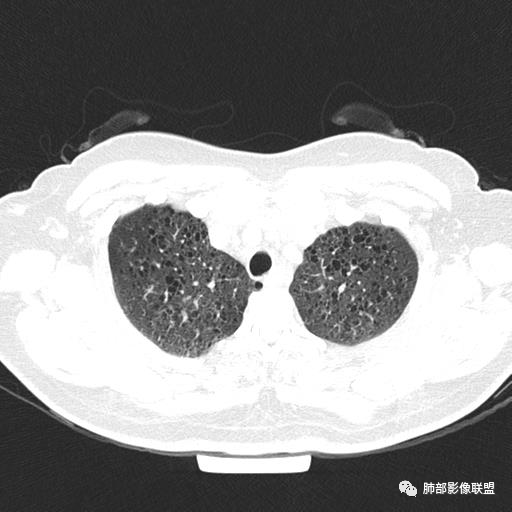

双肺弥漫囊腔,累及肋膈角,囊腔形态相对规则单一。

CT平扫示双肺弥漫分布大小不等囊状薄壁透光区,无内、中、外带分布差异,间质稍示增厚。拟LAM

中年女性育龄期妇女,咳嗽气喘,无吸烟史,有苯吸入史。影像:双肺弥漫均匀小囊腔,无明显分布优势,囊腔形态欠规则,壁薄,部分囊腔边缘血管征,伴双肺弥漫磨玻璃影,无结节,考虑lam,鉴别苯中毒肺损伤,囊腔多有分布优势,小叶中心分布为主,形态规整等

CT表现:双肺弥漫大小不等的薄壁囊腔,囊壁<2mm,外形规则,血管影多位于囊腔周围,囊腔之间肺组织正常,随着疾病进展到晚期,囊腔变大、增多,不可胜数,囊腔可融合成较大的囊,与肺气肿相似,形成间质性肺纤维化。部分病例可出现结节影。